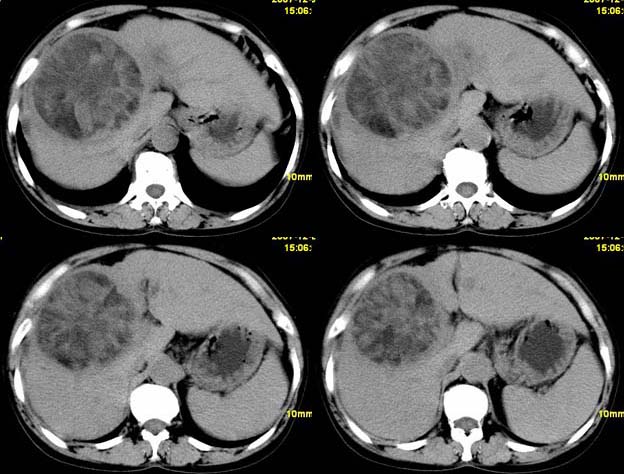

支持;肝aml-------脂肪成分,中心血管征,延时强化.